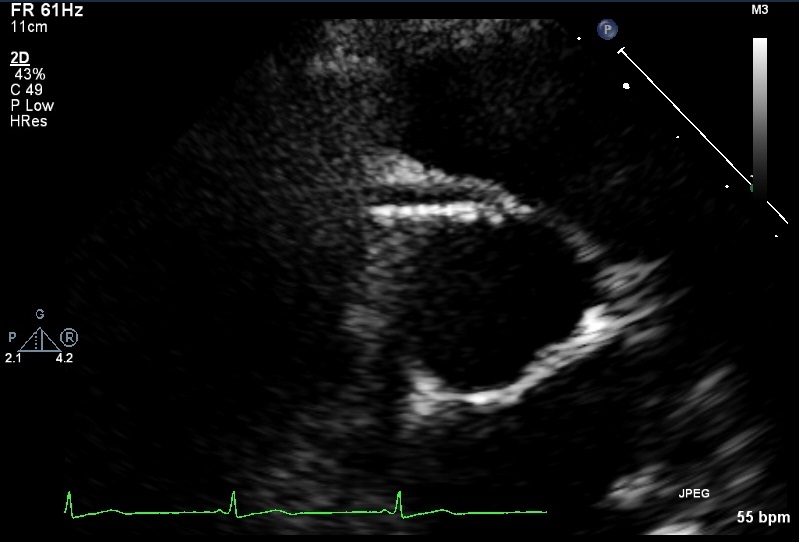

An example of TTDE in the short axis view with anatomical ... from www.researchgate.net The two main coronary arteries emanate from the aortic bulb (figure 1): This is a parasternal lv short axis at the basal level. Coronary artery fistulas are rare congenital or acquired coronary artery anomalies that can originate from any of the three major coronary arteries a transthoracic echocardiogram (figure 1a ) showed a continuous flow at color doppler analysis in the high parasternal short axis view, originating from a. Parasternal long axis right ventricular outflow landmarks (tilt toward left shoulder ). Short axis wall segments and coronary arteries. Methods coronary artery anatomy and relation of the great arteries were identified at angiography, echocardiography, surgical intervention or autopsy. Coronary artery disease (cad) causes impaired blood flow in the arteries that supply blood to the heart. Come back later and redeem yourself!

Coronary artery , echocardiogram, echo , short axis, left main, rcc, lcc, ncc , tricuspid. Objectives we studied the correlation between coronary artery pattern and aortopulmonary rotation in complete transposition of the great arteries. Short axis wall segments and coronary arteries. This is a parasternal lv short axis at the basal level. The right and the left.

Parasternal short-axis view showing anomalous origin of ... from www.researchgate.net Ultrasound machines typically have combined echo measurements. Information on coronary balloon angioplasty and stents. All three of the following measurements are typically recorded by. 0:04 stella and juz mcginn bowra 3 056 просмотров. Parasternal short axis echocardiography images for diagnosing anomalous right coronary artery from the left coronary artery congenital heart defects. * * left and right coronary artery are seen in this views just superior to the aortic annulus extending from left and right. • suprasternal notch (optimal neck extension). If the beam is angled superior to the aortic valve, the ostia of the left main and right coronary arteries, usually at 4 and 11 o'clock respectively, can be present.

All three of the following measurements are typically recorded by. Healthy coronary arteries are smooth and elastic. You didn't really mean to click that, did you? Essential echocardiography a companion to braunwald's heart disease. Echo plays an increasingly important role in assessing coronary artery disease. 1:25 sie hing tang 15 466 просмотров. Coronary artery , echocardiogram, echo , short axis, left main, rcc, lcc, ncc , tricuspid. Coronary artery disease (cad) causes impaired blood flow in the arteries that supply blood to the heart. * * left and right coronary artery are seen in this views just superior to the aortic annulus extending from left and right. Information on coronary balloon angioplasty and stents. This view is useful in helping with the diagnosis of mitral stenosis and congenital heart disease, among others. Parasternal long axis right ventricular outflow landmarks (tilt toward left shoulder ). This is a parasternal lv short axis at the basal level.

Ultrasound machines typically have combined echo measurements. Gross anatomy origin the right coronary artery (rca) ostium arises from the right sinus of valsalva, found between the aorti. The right coronary artery (rca) is one of the two main coronary arteries that supply the heart with oxygenated blood. Coronary artery disease (cad) is the leading cause of death in the united states. Coronary artery fistulas are rare congenital or acquired coronary artery anomalies that can originate from any of the three major coronary arteries a transthoracic echocardiogram (figure 1a ) showed a continuous flow at color doppler analysis in the high parasternal short axis view, originating from a. Read about symptoms and tests. 1:25 sie hing tang 15 466 просмотров. Headaches and dizziness online course: Information on coronary balloon angioplasty and stents. Essential echocardiography a companion to braunwald's heart disease. The coronary arteries wrap around the outside of the heart. * * av morphology determined at this view. This is the most basal short axis view that sometimes slight angulation will allow visualization of the left main and right coronary arteries.

Parasternal short axis echo | lesson #157, part of our free online sonography training modules coronary arteries. Coronary artery fistulas are rare congenital or acquired coronary artery anomalies that can originate from any of the three major coronary arteries a transthoracic echocardiogram (figure 1a ) showed a continuous flow at color doppler analysis in the high parasternal short axis view, originating from a.